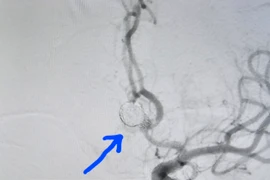

Người phụ nữ 47 tuổi sau khi tắm đột ngột đau đầu dữ dội kèm nôn ói vì xuất huyết dưới nhện do vỡ túi phình mạch máu não. May mắn, bệnh nhân được các bác sĩ cứu sống kịp thời.

Sau tắm hôn mê do vỡ túi phình mạch máu não

Phương pháp điều trị phình mạch máu não hiệu quả, tránh vỡ gây tử vong

Phình mạch máu não là căn bệnh tiềm tàng nguy hiểm, nếu không được phát hiện và điều trị, khi vỡ sẽ rất nguy hiểm, để lại nhiều biến chứng nặng nề, thậm chí là tử vong.